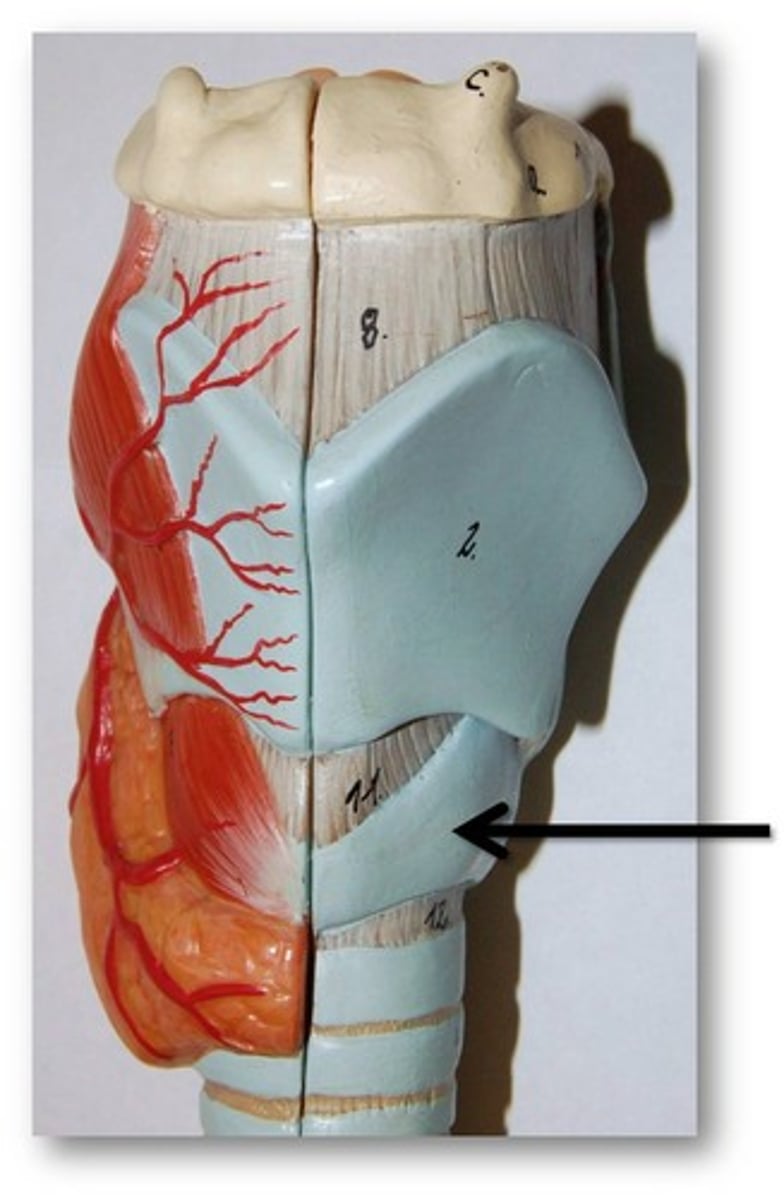

Larynx

Voice box; passageway for air moving from pharynx to trachea; contains vocal cords

Laryngeal Cartilages

Largely construct the larynx (voice box)

Cricoid Cartilage

The ring-shaped structure that forms the lower portion of the larynx

Trachea

A large membranous tube reinforced by rings of cartilage, extending from the larynx to the bronchial tubes and conveying air to and from the lungs; the windpipe.